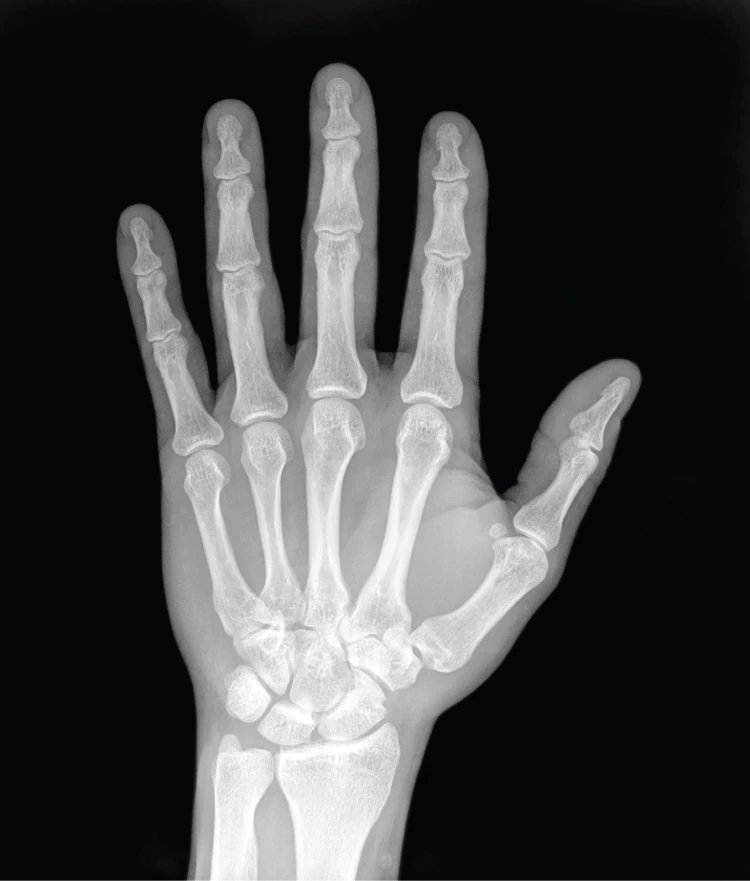

X선 촬영 사진 : 통과한 물체는 검은색으로 보인다.

방사선은 필름에 닿으면 검은색으로 보이게 하는 특징이 있습니다. 방사선 중 X선은 공기를 잘 관통하기 때문에 통과할 대상이 없는 방사선의 사진을 보면 검은색으로 보입니다. 하지만 뼈는 거의 통과하지 못하므로 방사선이 닿지 않아 하얀색으로 보이죠. 물이나 지방은 잘 관통하지 못해서 회색으로 나오기도 하고요.

만약 뼈가 부러졌으면 그 부러진 부위는 X선이 통과하기 때문에 검거나 회색의 선으로 나타나게 되므로 사진을 통해 뼈가 부러졌는지를 알 수 있어요. 또한 원래 아무것도 없어서 검은색으로 나타나야 하는 부위에 하얀색 혹이 나타났다면 종양이 생겼다는 것을 알 수 있기도 합니다. 하지만 방사선은 인체에 해롭기 때문에 한 번에 많은 양이 몸속에 들어오면 안 됩니다.

그런데 우리 눈에는 멀쩡하게 보이는 피부는 X선 사진에서는 없는 것으로 나타납니다. 뼈와 지방 이외에는 다 검은색으로 표시되기 때문이에요. X선이 물체를 통과하기 위해서는 물체 내부의 원자를 통과해야 하는데, 이때 원자 외부의 전자와 충돌하면서 에너지를 뺏기게 됩니다. 따라서 물체 내부의 전자가 많을수록 X선이 이동하기가 어려워져 결국 투과할 수 없게 됩니다. 우리 피부의 대부분은 주로 탄소, 수소, 산소 등 유기 물질로 구성된 연질 조직으로 상대적으로 전자가 적어요. 수소는 원자핵 주변의 전자가 하나밖에 없지요. 하지만 칼슘으로 만든 뼈나 치아는 매우 단단하면서 전자가 많아 X선이 통과하기 어렵습니다.